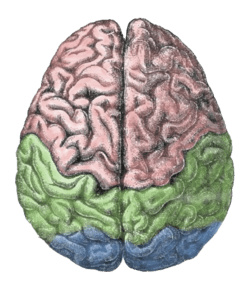

Search q draw e0 a4 ae e0 a4 be e0 a4 a8 e0 a4 b5 e0 a4 ae e0 a4 b8 e0 a5 8d e0 a4 a4 e0 a4 bf e0 a4 b7 e0 a5 8d e0 a4 95 e0 a4 95 e0 a4 be e0 a4 a8 e0 a4 be e0 a4 ae e0 a4 be e0 a4 82 e0 a4 95 e0 a4 bf e0 a4 a4 e0 a4 9a e0 a4 bf e0 a4 a4 e0 a5 8d e0 a4 b0 e0 a4 b9 e0 a4 bf e0 a4 82 e0 a4 a6 e0 a5 80 tbm isch (फाइल का प्रकार jpg)